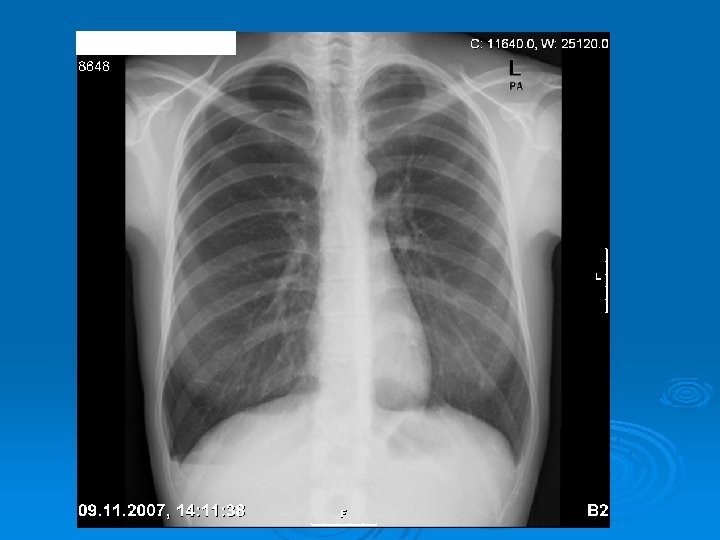

Ø Physical examination: l l l Ø Hypersonority on percusion Reduced breath sounds, reduced VT, enlarged hemithorax Hypotension and cardiac tamponade may occur depending on the size of the pneumothorax Radiology: l l Pleural line Hyperlucency at the periphery Mediastinal shift Expiration film can be used when the lesion is not apparent